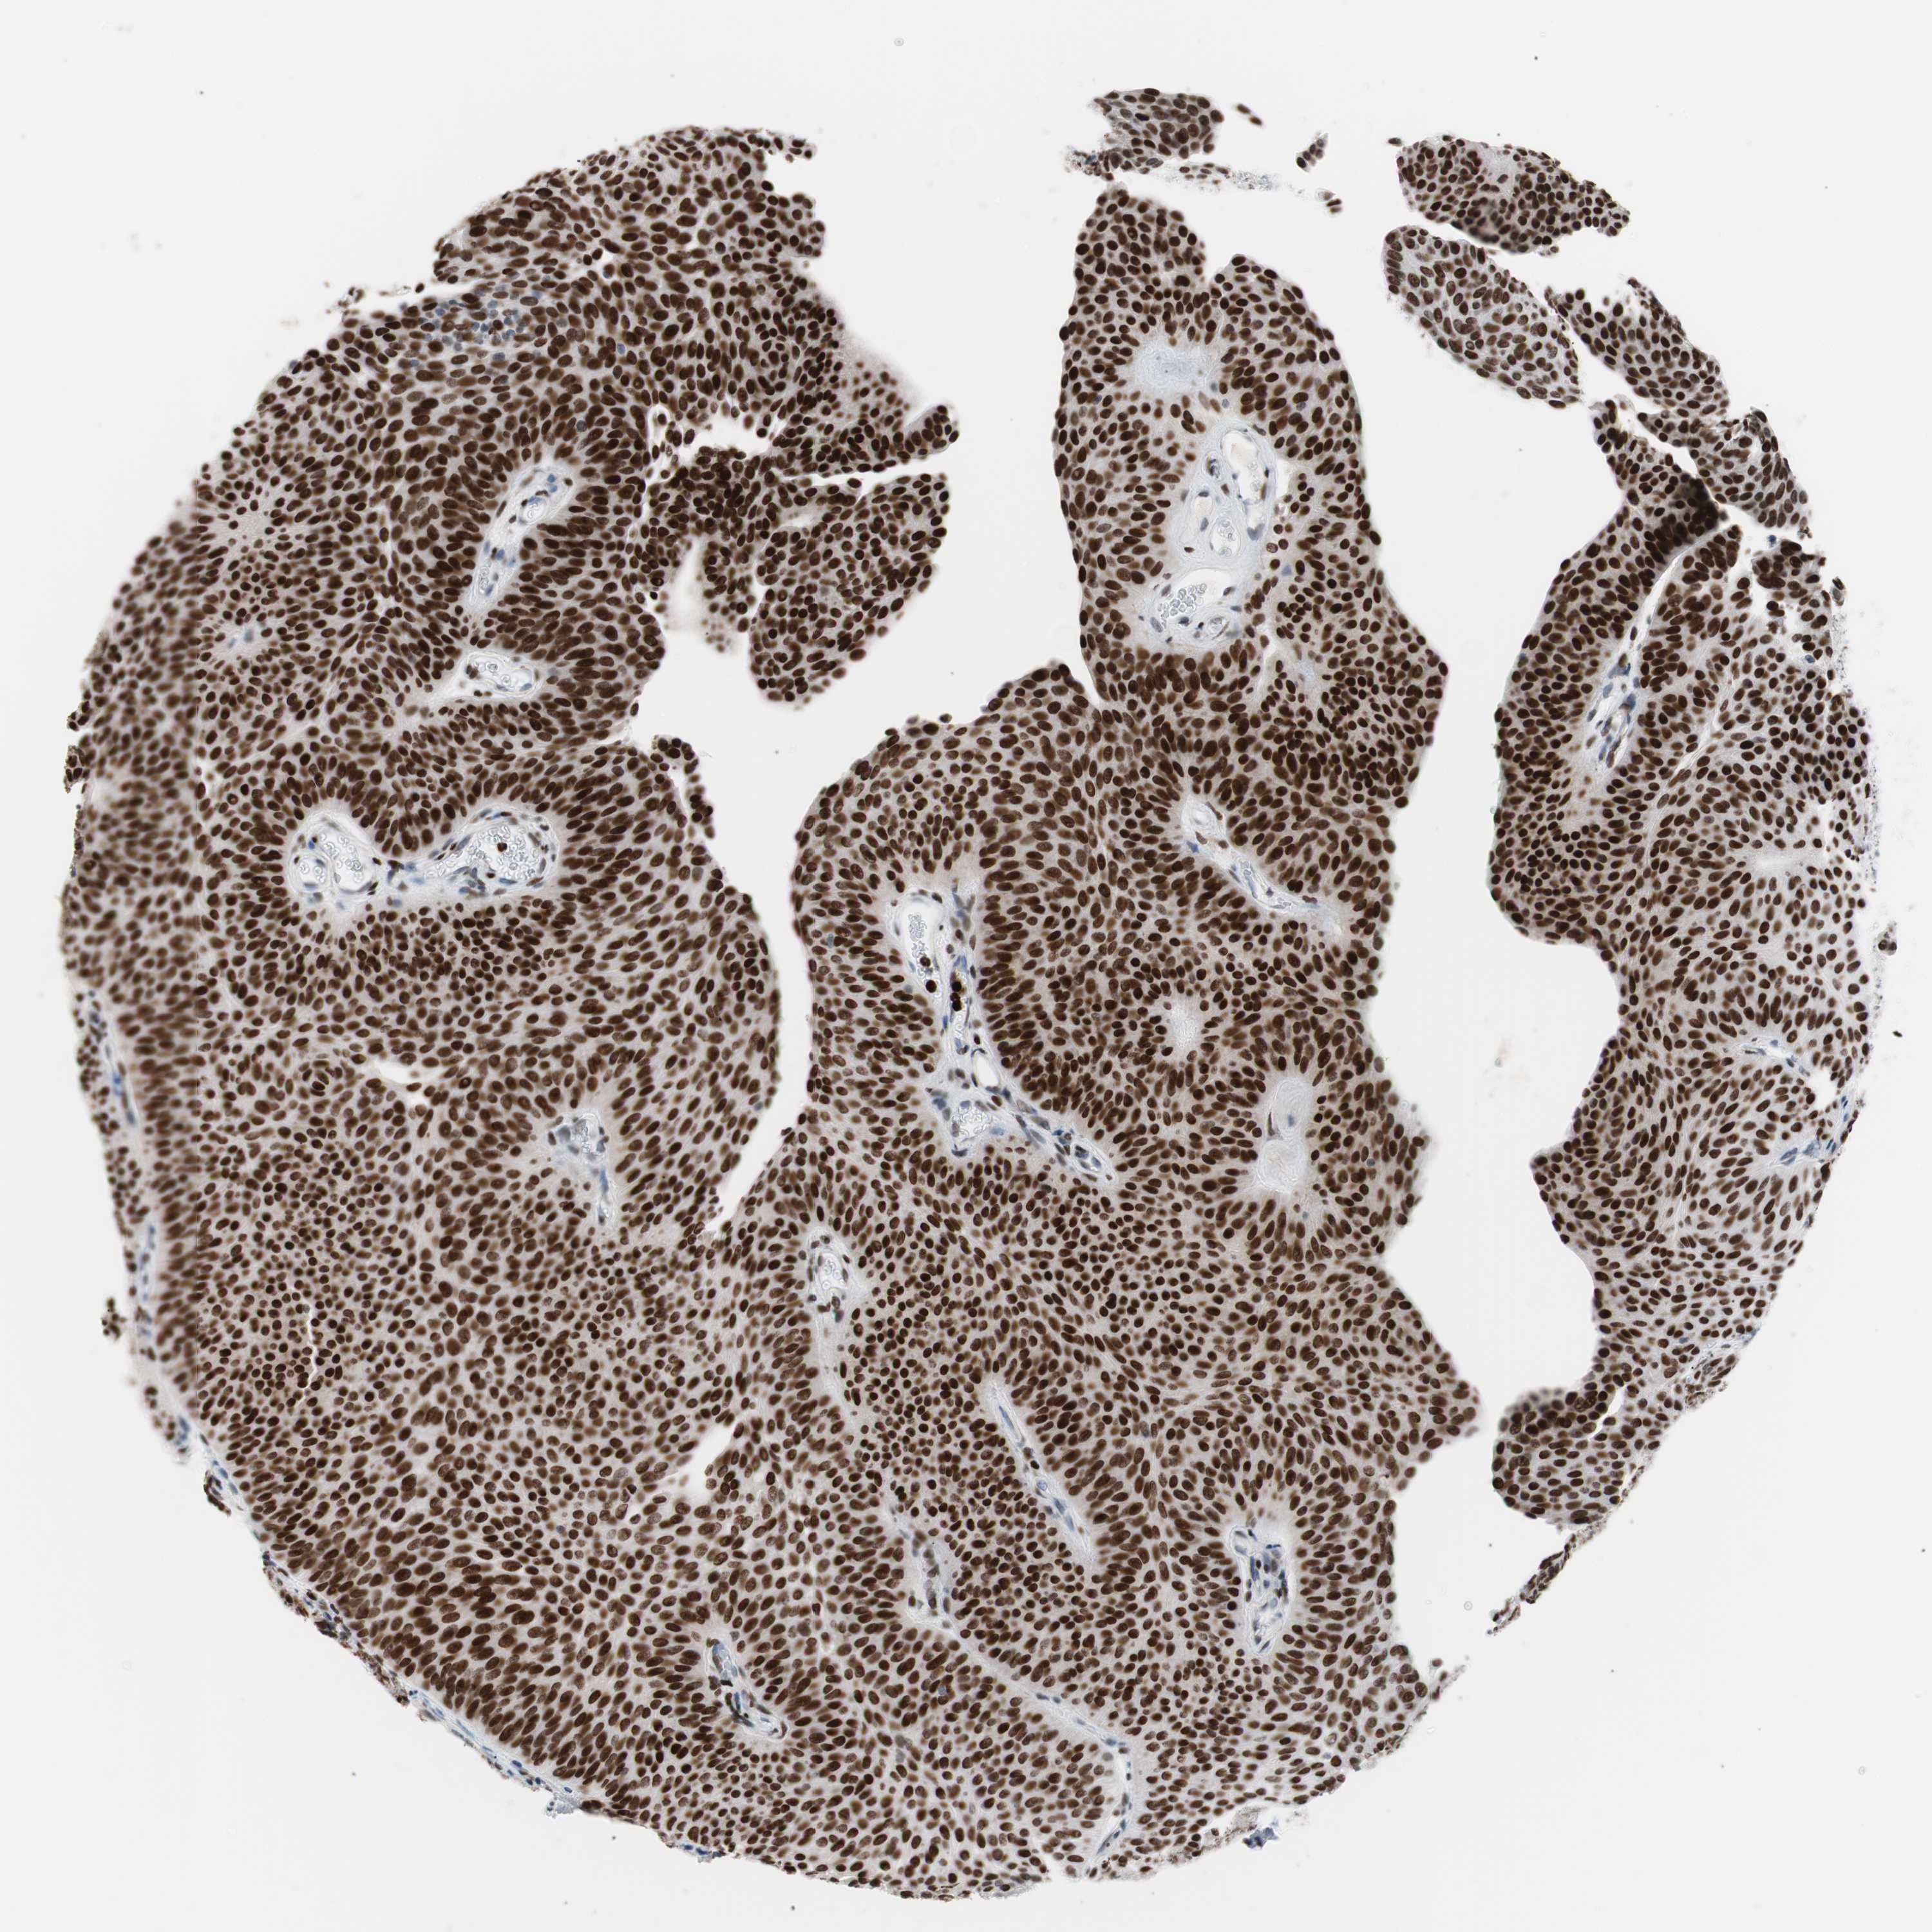

UROTHELIAL CANCER - Protein expressioni

A mouse-over function shows sample information and annotation data. Click on an image to view it in a full screen mode. Samples can be filtered based on level of antibody staining by selecting one or several of the following categories: high, medium, low and not detected. The assay and annotation is described here.

Note that samples used for immunohistochemistry by the Human Protein Atlas do not correspond to samples in the TCGA dataset.

Antibody stainingi

Antibody staining in the annotated cell types in the current human tissue is reported as not detected, low, medium, or high, based on conventional immunohistochemistry profiling in selected tissues. This score is based on the combination of the staining intensity and fraction of stained cells.

Each image is clickable and will lead to virtual microscopy that enables deeper exploration of all samples and also displays staining intensity scores, fraction scores and subcellular localization as well as patient and tissue information for each sample.

Antibody CAB004213

Staining

High

Strong

Quantity

Location

Urothelial carcinoma, Low grade

Urothelial carcinoma, High grade